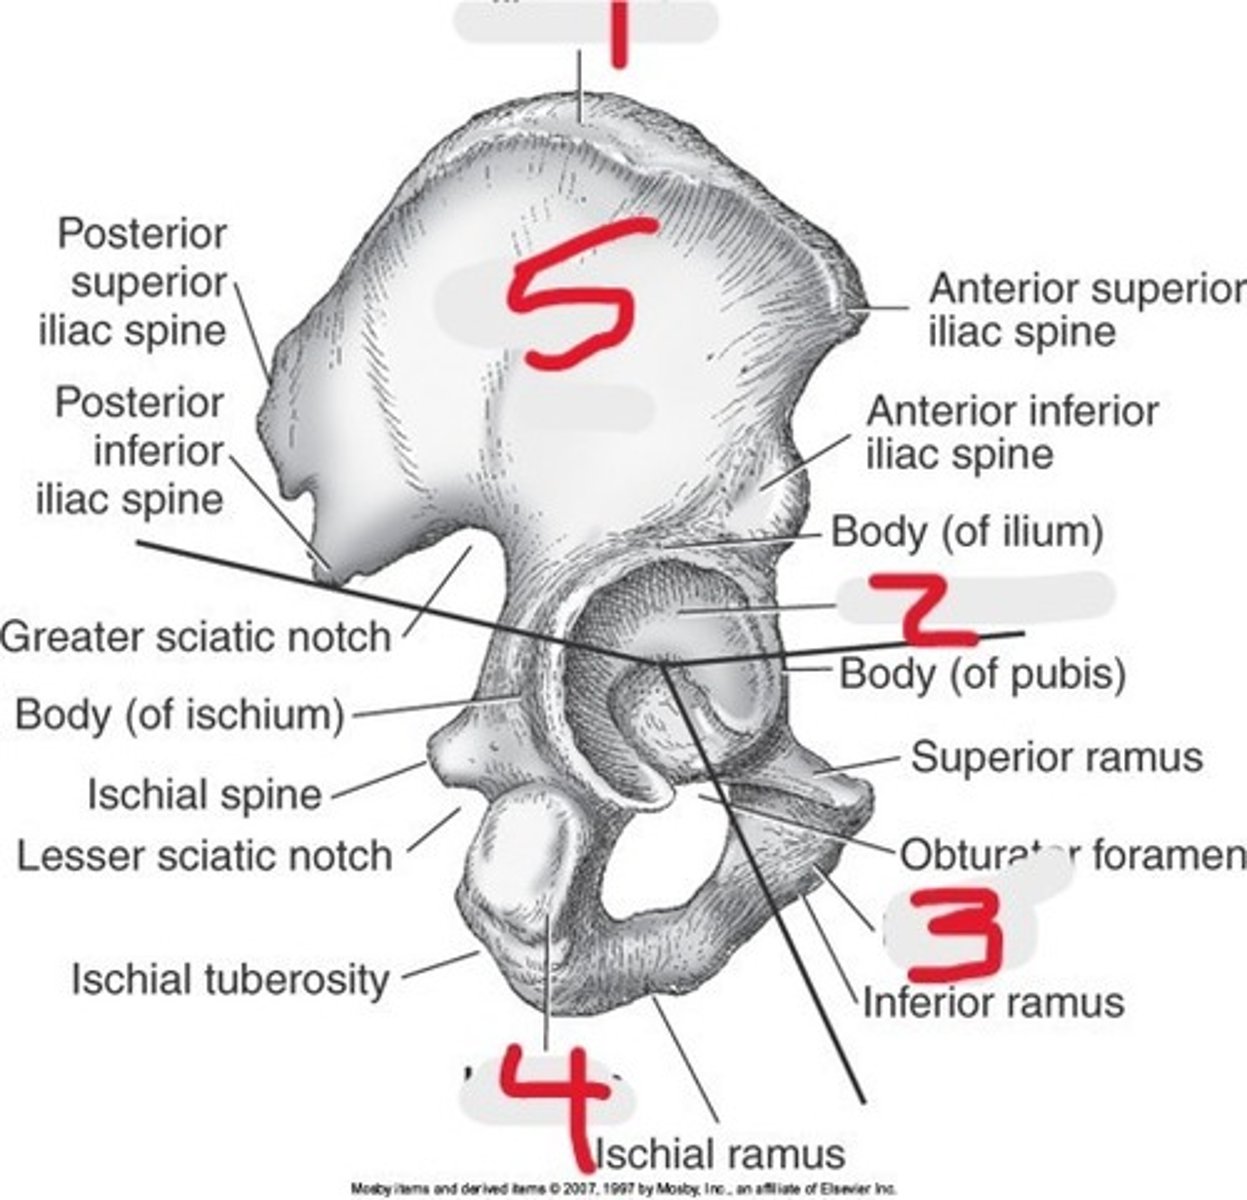

1) Ilium

2) Ischium

3) Pubis

What 3 bones make up the os coxae

Name all numbered structures

Ilium

This is the largest and most superior portion of the bony pelvis

T or F: The ilium has a body

The ala

This is the large wing-like portion of the ilium

The iliac crest

This is the superior ridge of the ala of the ilium

The body of the ilium

This creates the superior portion of the acetabulum

Acetabulum

This structure of the pelvis articulated with the head of the femur

The ischium

This is the inferior portion of the os coxae

1) Body

2) Two rami

What composes the ischium (2)

Ischium

This forms the inferior portion of the acetabulum

1) Ischium

2) Ilium

3) Pubis

Name all numbered structures

The pubis

This forms the lower, anterior portion of the acetabulum

1) Body

2) Two rami

What is the pubis composed of (2)

Pubic bones

The bodies of the two _______ meet at the midline to form the pubic symphysis

The union of the pubic rami and the ischium

This forms the obturator foramen